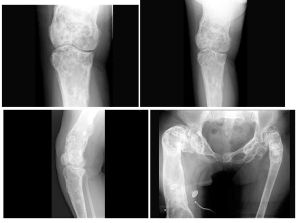

蠟油樣骨病從X線平片看出,蠟油樣骨病患者的髖部主要表現為一側髖關節兩端骨質增生硬化,呈斑片狀或團塊狀高密度影,病變可跨越髖關節.但關節腔及關節面保持正常,髖關節周圍軟組織口見異位骨化。表現為骨內有斑點狀或條紋狀緻密影,不易引起輪廓改變,關節多不受影響,即使關節兩端骨質發生明顯新骨堆積,關節面仍保持光滑,附近軟組織中常有骨質沉積。

圖a為右髂骨X光平片、髖臼上緣及股骨近端斑塊狀骨質增生硬化,境界清楚。

圖b為右髂骨CT平掃,除清楚顯示股骨近端表面骨質增生外.髖關節周圍軟組織內亦見團塊狀異位骨化,關節腔正常,關節面依然保持光滑。